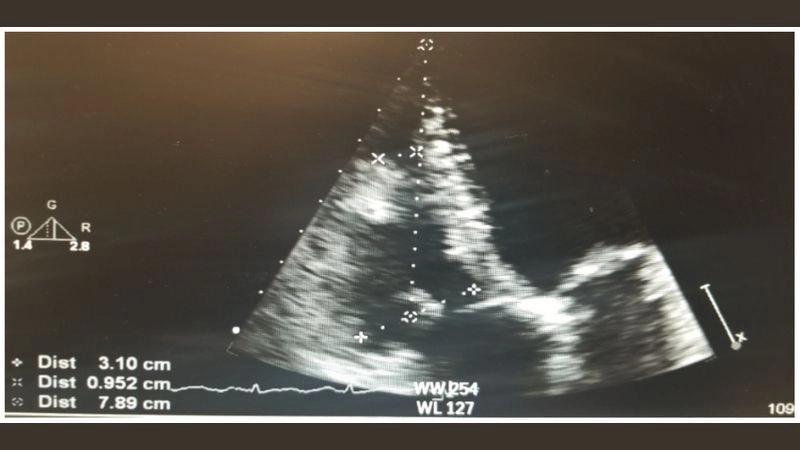

Images visual examples of rhabdomyoma

Rhabdomyoma is a rare benign tumor of striated muscle, commonly affecting the heart in children. Images often highlight cardiac masses that disrupt heart rhythm and function.

Precise image for rhabdomyoma diagnosis clarity